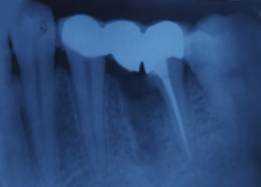

Immediate Post-Surgical IOPAR